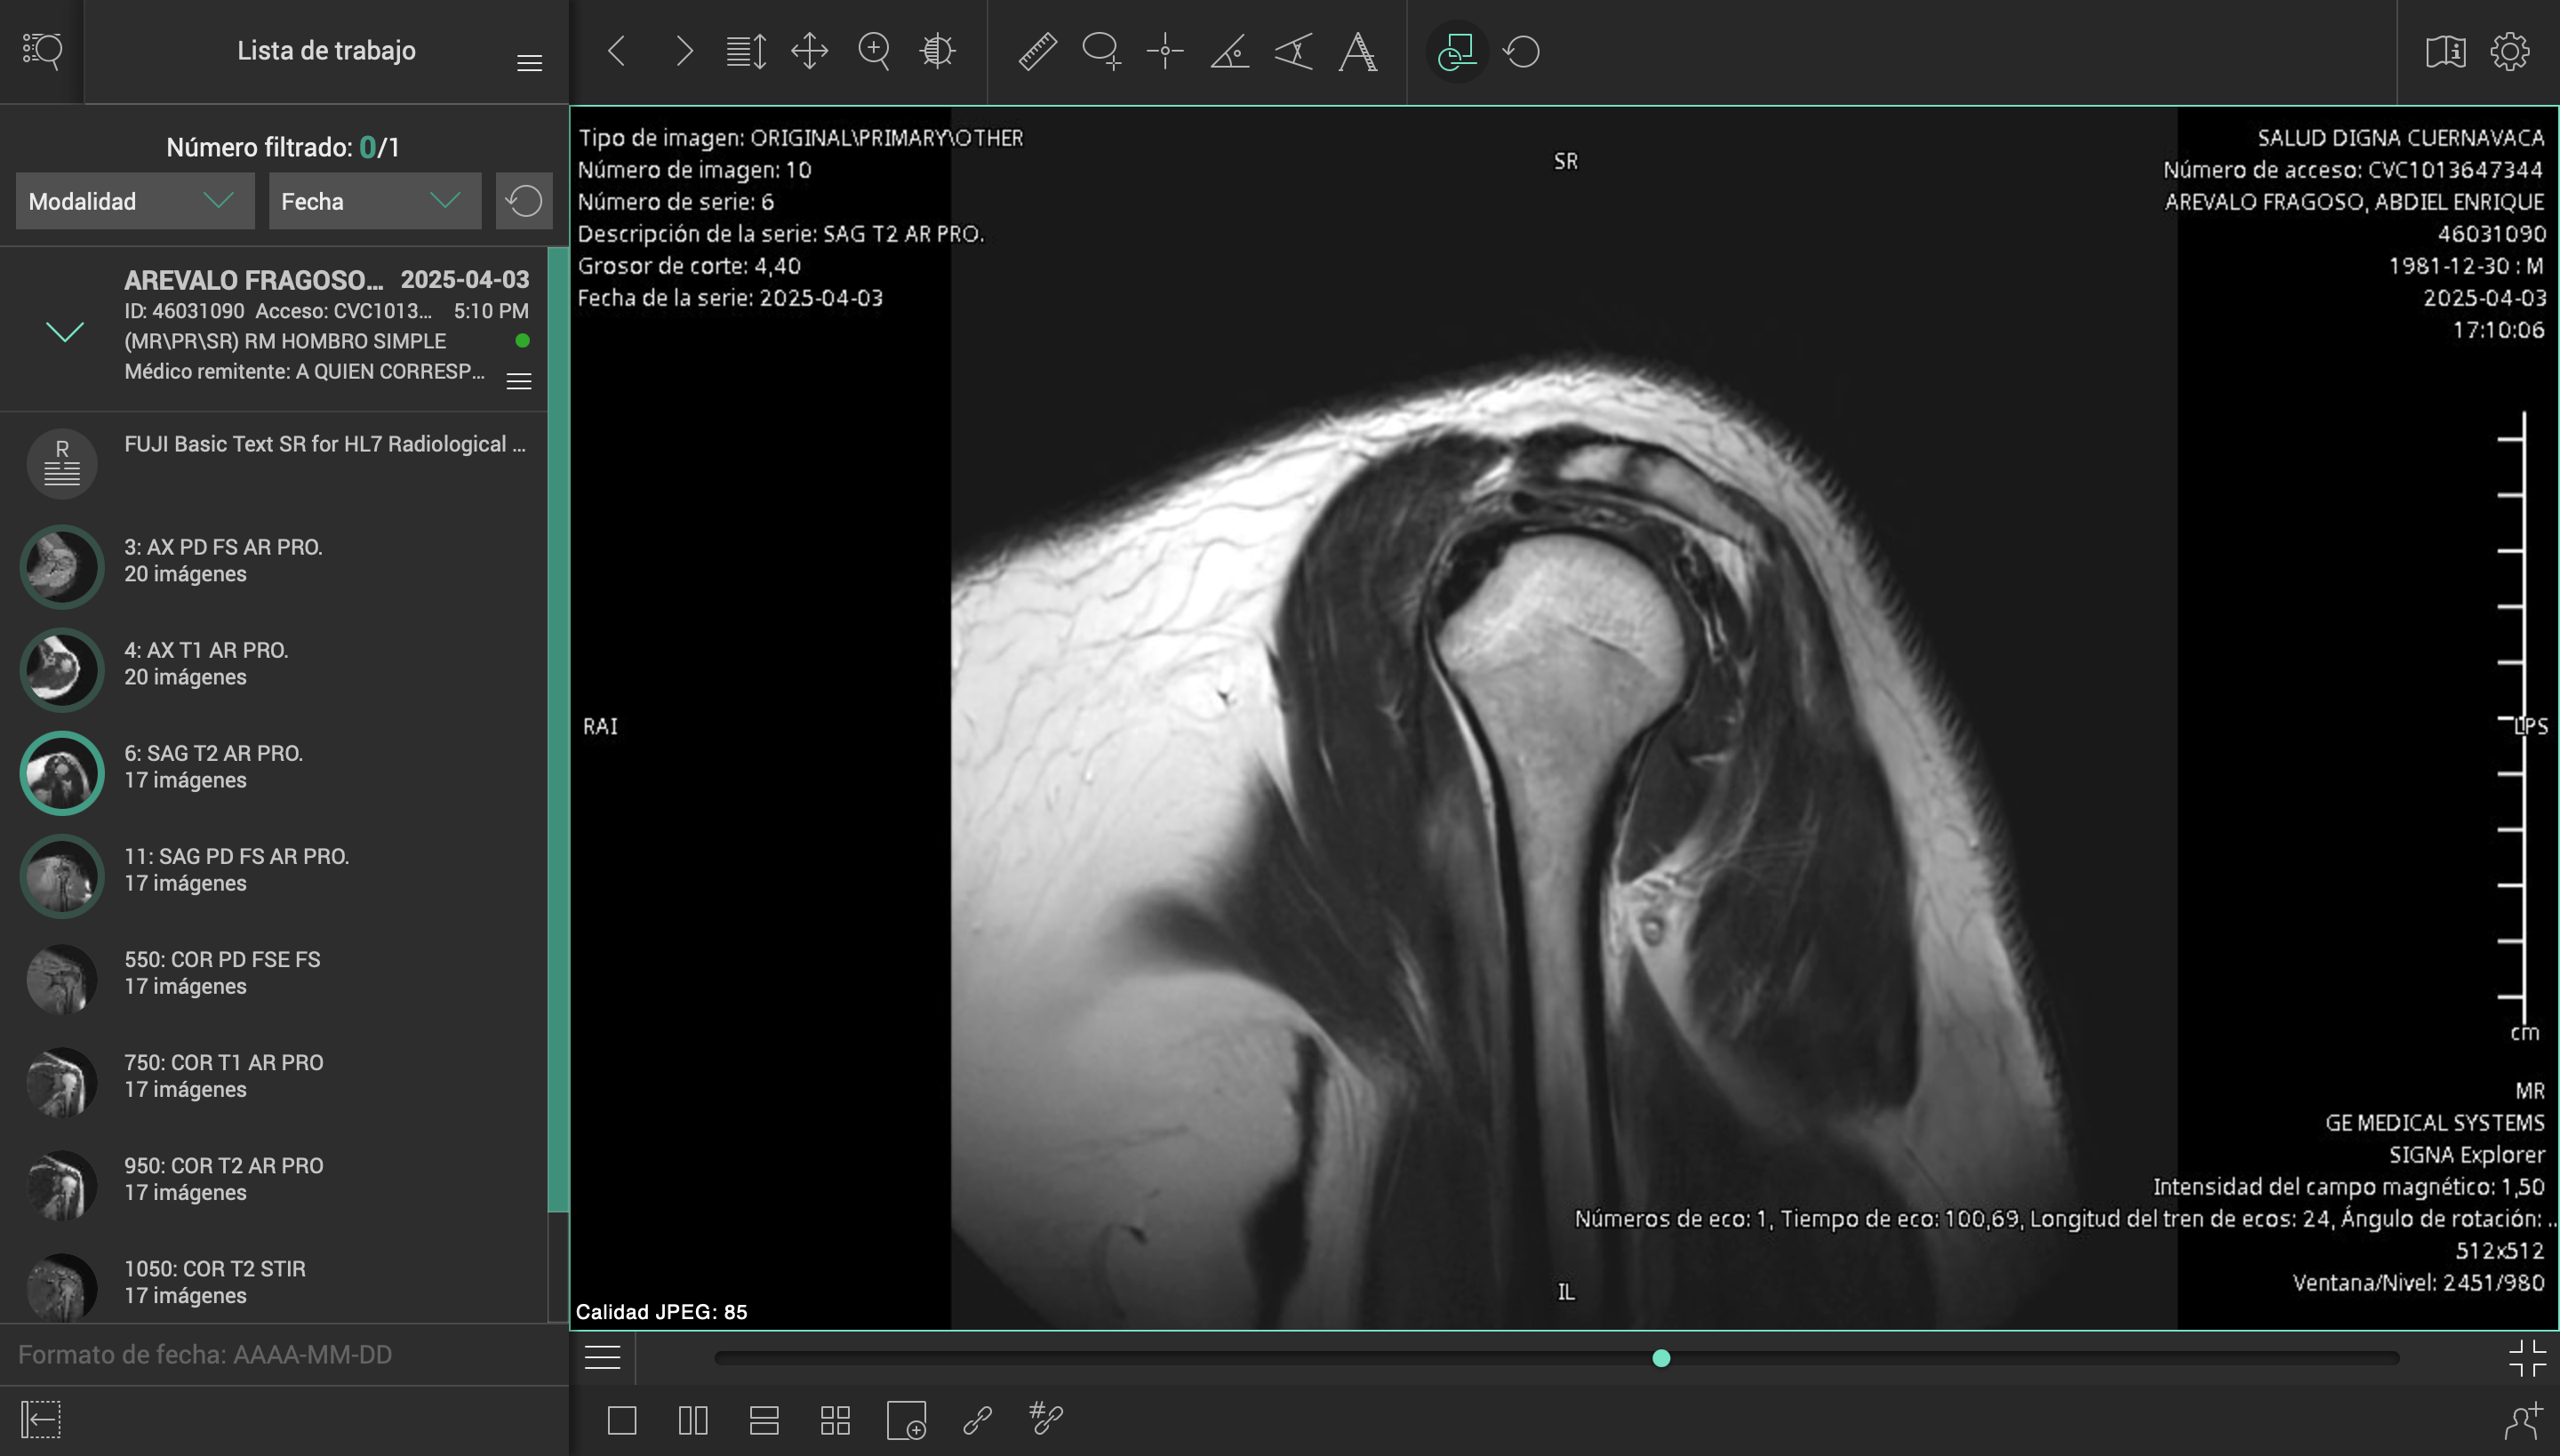

El pasado 2 de marzo de 2025, sufrí un accidente en carretera mientras conducía mi motocicleta. Un automóvil me impactó y me arrojó contra el asfalto, causándome lesiones severas en el hombro izquierdo, columna cervical y lumbar. El conductor se dio a la fuga, y hasta ahora no ha sido posible obtener justicia ni apoyo institucional.

Desde entonces, han pasado más de tres meses esperando una consulta con un especialista del ISSSTE, sin éxito. Durante este tiempo, mi salud ha empeorado, con complicaciones cada vez mayores por la falta de atención médica oportuna.

Esta situación me ha colocado en una condición muy vulnerable, médica, emocional y económicamente. Los tratamientos, terapias y cirugías necesarias superan los casi un millón de pesos mexicanos, una cifra que me resulta imposible cubrir por mi cuenta.

Es por ello que me veo en la necesidad de iniciar este fondeo, para poder comenzar al menos con la primera parte del tratamiento, y frenar el avance de las lesiones, mientras buscamos cómo costear el resto de la atención médica que necesito para recuperar mi salud y movilidad.